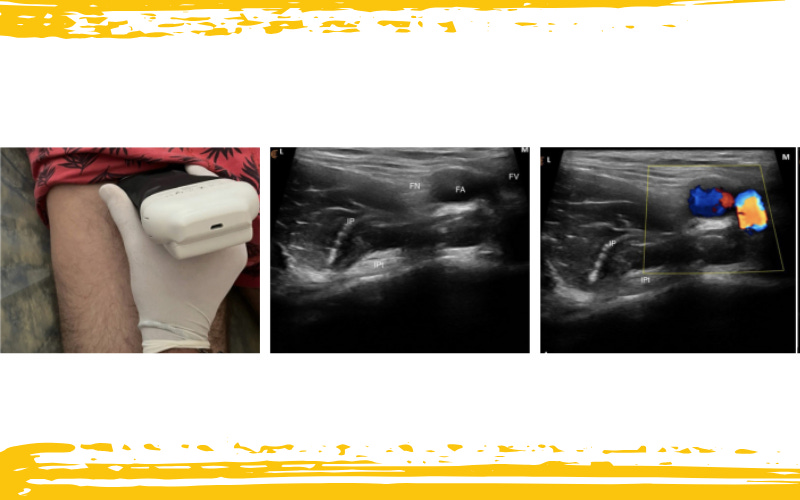

Para visualizarlo, el transductor se coloca transversalmente a la articulación de la cadera.

Luego, al desplazarse medialmente, aparece el músculo pectíneo, adherido al ramo púbico superior, justo medial a la vena femoral.

Infografía 1. Colocación transversal de la sonda de ecografía en la articulación de la cadera, con visualización de las estructuras vasculares.

M – medial; L – lateral; P – proximal; D – distal; AL – músculo aductor largo;

AB – músculo aductor corto; AM – músculo aductor mayor; IP – músculo iliopsoas;

Ipt – tendón del iliopsoas; FA – arteria femoral; FV – vena femoral;

FN – nervio femoral; OE – músculo obturador externo; Pec – músculo pectíneo;

SPR – ramo púbico superior.